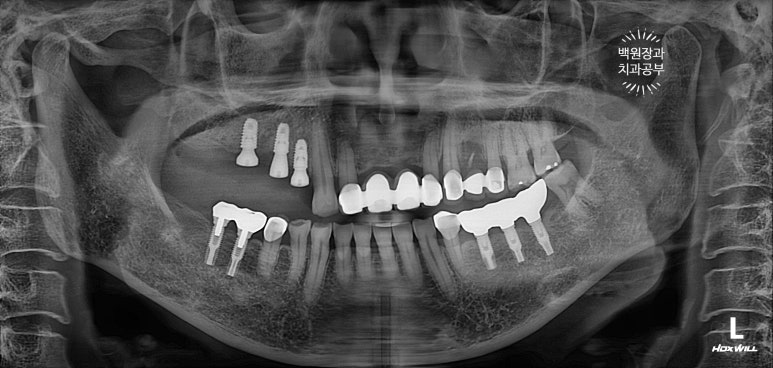

오른쪽 위 임플란트 2개를 약 10년 전에 수술하신 분입니다.

노란색으로 동그라미 쳐져 있는 부위의 임플란트 주변 잇몸에서 고름이 나온다고 하셨어요.

이미 잇몸뼈는 주황색 선처럼 매우 많이 사라져 버린 상태..... 이미 임플란트 주변 뼈는 모두 사라져 빠지기 직전.

보시면 녹색 별로 표시한 자기치아도 주변 뼈가 이미 많이 없어진 것을 보실 수 있습니다.

임플란트 주위염이 심해지면 주변 자연치아도 못쓰게 됩니다. 정기검진을 꼭 다니셔야하는 이유입니다.

뼈이식을 하고나서 촬영한 치과용 파노라마 사진입니다.

뼈이식재가 엄청나게 잘 위치된 것을 볼 수 있습니다. 마치 뼈가 하나도 없어지지 않았던 것처럼......

보시면, 처음 뼈이식했던 것보다는 임플란트가 다소 깊이 위치한 것을 보실 수 있죠?

왜냐면, 아까 얘기했듯이 우리가 사용했던 뼈이식재가 100프로 모두 잇몸뼈가 되지 않기 때문이죠.